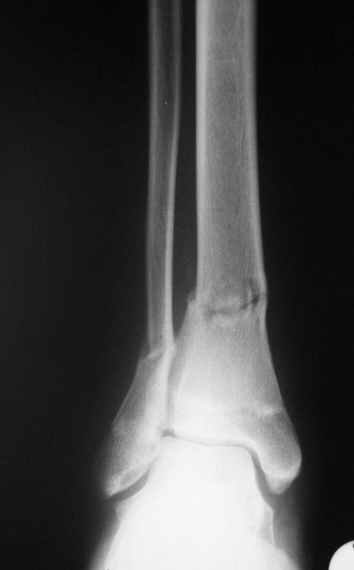

дистальный тиб.фиб. перелом

Уважаемые коллеги,Больной 17 лет , 3 недели с момента травмы, был переведен в наше отделение из соседнегогоспиталя.

Попытка закрытой ручной репозиции, предпринятая ранее в этой больнице,оказалась безуспешной, что и явилось причиной перевода к нам.Чтобы вы предложили в данной ситуации?Показана ли фиксация перелома малоберцовой кости в данном случае или в этом нет необходимости?Евгений Чекашкин

На прямой проекции видно угловое смещение отломков малоберцовой кости, обуславливающий и

наклон тарана, да и вальгус отломков б.б. , а на боковой проекции -смещение отломков

кпереди и по длине.

Коррекция углового смещения и смещения по длине отломков м.б. кости автоматом устраняет

наклон тарана , что необходимо для нормальной функции голеностопа. Так оно и произошло во

время операции.

Единственный момент, о котором я и уже писал - не наступило спонтанной анатомичной

репозиции отломков б.б., поэтому после репозиции пришлось использовать тягловый винт и

*укрепить* достигнутое положение узкой пластиной динамической компрессии.

Послеоперационные снимки сегодня посмотрел - все выглядит вполне анатомично, кроме длины

винтов на м.б. кость - слегка переборщил:-(( Не было камеры с собой , но как только

пересниму картинки обязательно вышлю.

Поэтому фиксация м.б. кости все-таки показана....